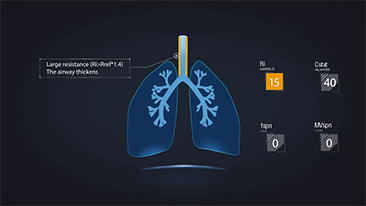

Choosing the correct ventilator settings for treating patients with respiratory tract disease is an important issue. Since the task of specifying the parameters of ventilation equipment is entirely carried out by a physician, their knowledge and experience in the selection of these settings has a direct effect on the accuracy of their decisions. There are numerous ventilation modes and decision-supporting tools which have been developed specifically to help caregivers improve efficiency and eliminate errors in clinical decision-making.

Integrating high-flow oxygen therapy, non-invasive ventilation and invasive ventilation, the 3-in-1 SV Series ventilators bring together stable performance, versatile functions and ease of use. Exceptional lung protective features and decision-support tools are designed to reduce the risk of cross-infection and reduce caregiversŌĆÖ workloads.